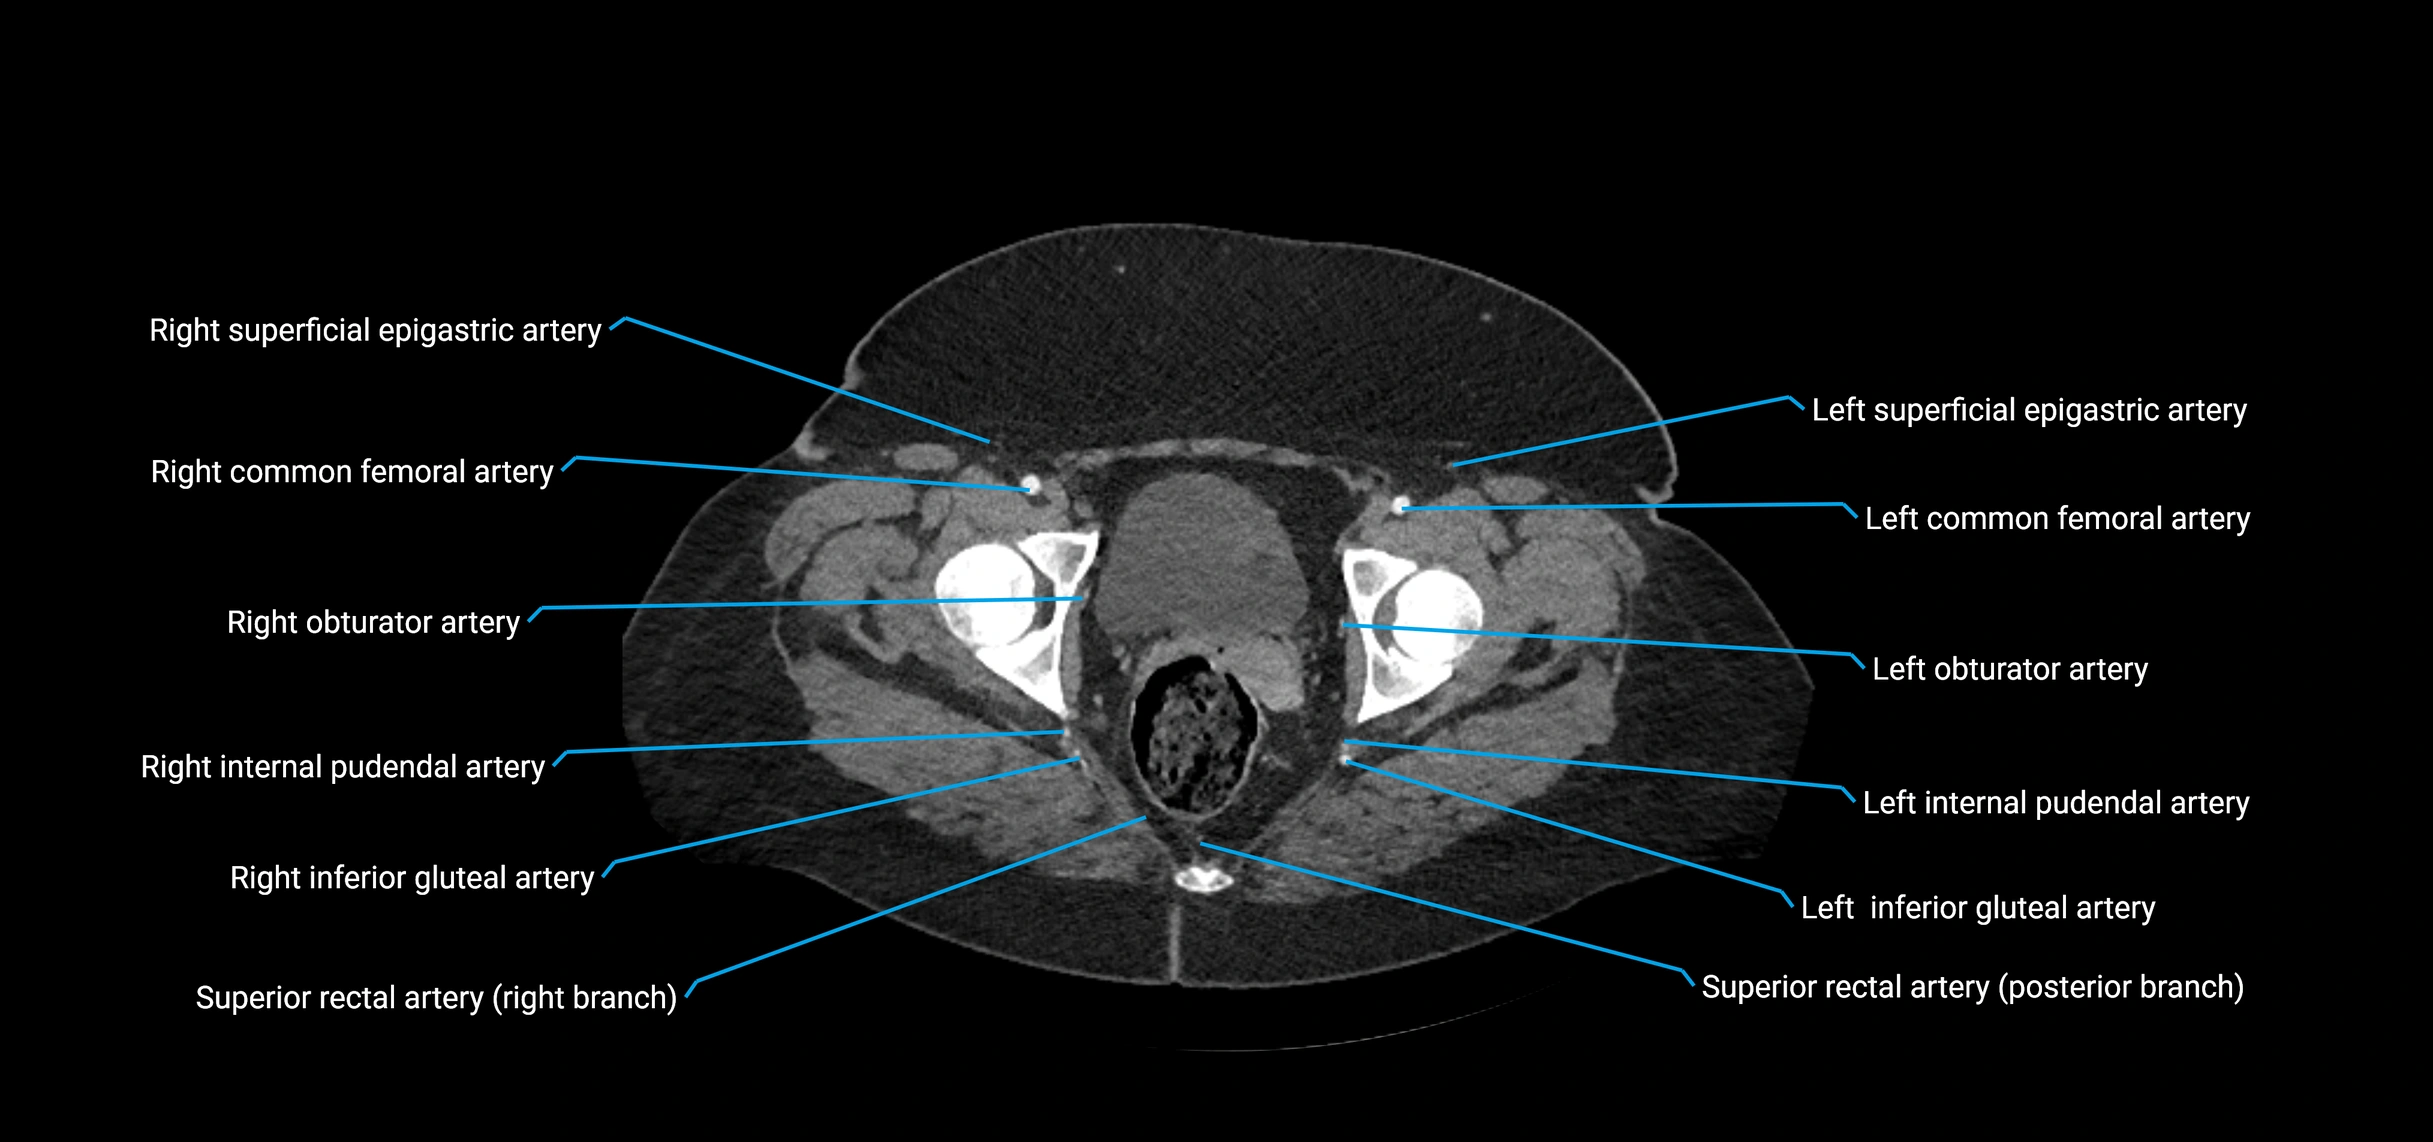

Contrast-enhanced CT (CTA):

• Gold standard for abdominal aortic imaging

• Provides excellent detail of lumen, wall, aneurysm, thrombus, and branch vessels

• Multiplanar and 3D reconstructions help in aneurysm measurement, stent graft planning, and dissection evaluation

• Detects acute rupture, traumatic injury, or occlusion with high sensitivity